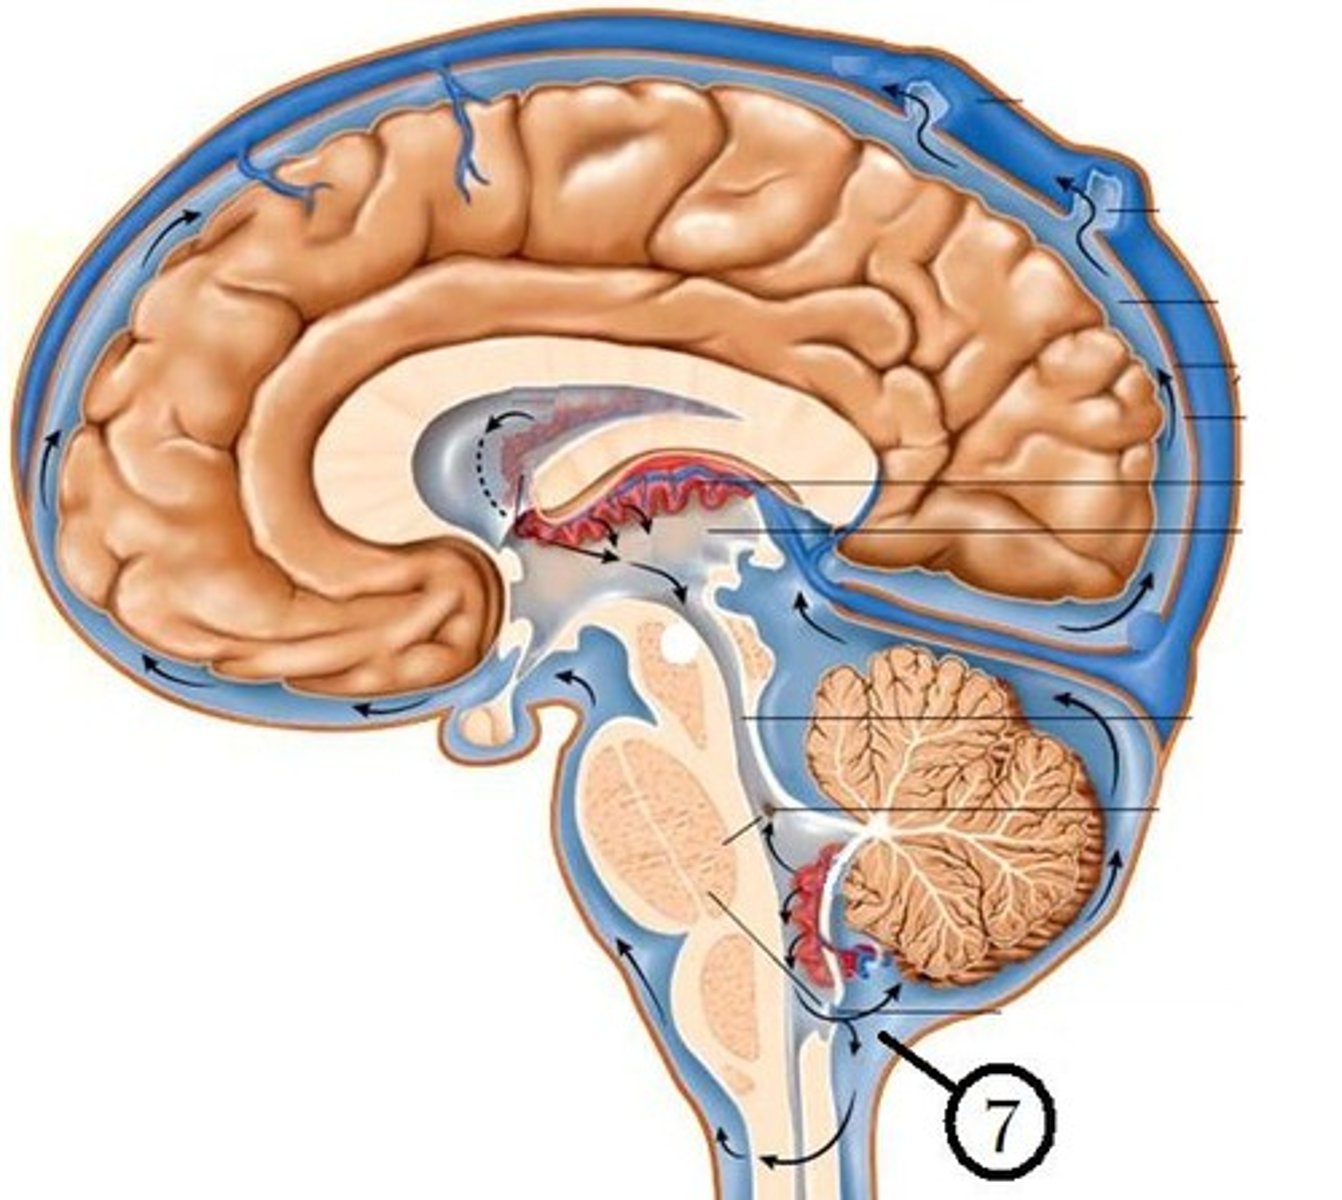

cerebrospinal fluid (CSF)

plasma-like clear fluid circulating in and around the brain and spinal cord

Production of CSF

begins with the filtration of blood plasma through the capillaries of the brain

Ependymal cells modify the filtrate, so CSF has more sodium and chloride than plasma, but less potassium, calcium, glucose, and very little protein

HAPPENS IN ALL VENTRICLES

CSF circulates through

lateral ventricles to third ventricle to cerebral aqueduct to fourth ventricle to subarachnoid space and central canal of spinal cord

choroid plexus

A highly vascular portion of the lining of the ventricles that secretes cerebrospinal fluid.

lateral ventricle

one of the two ventricles located in the center of the telencephalon

third ventricle

the ventricle located in the center of the diencephalon

cerebral aqueduct

connects the third and fourth ventricles

fourth ventricle

the ventricle located between the cerebellum and the dorsal pons, in the center of the metencephalon

central canal of spinal cord

center of spinal cord which contains cerebrospinal fluid

continuous with 4th ventricle

Drainage of CSF

into dural sinuses via arachnoid granulations